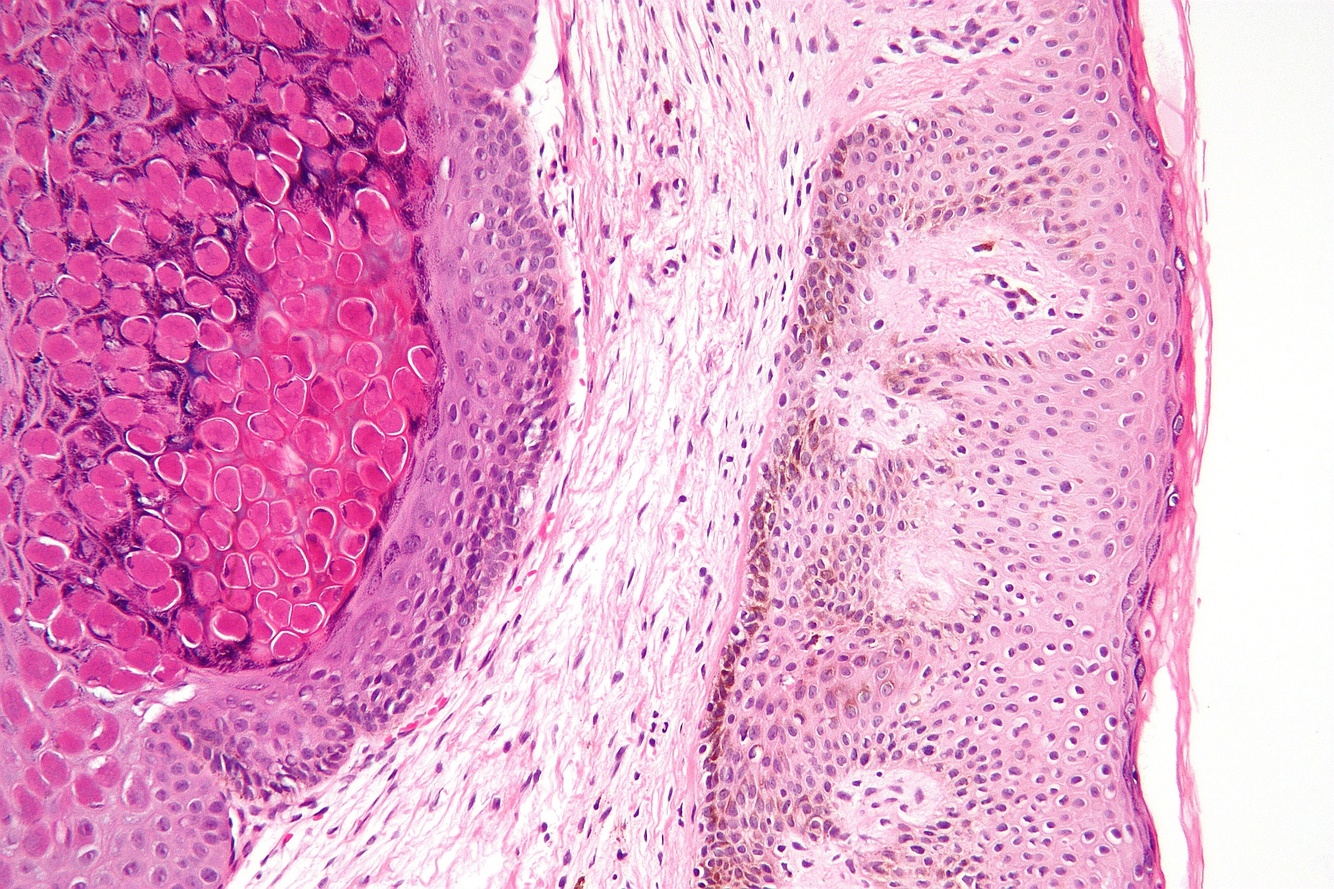

Squamos Papilloma

Benign proliferation of STRATIFIED SQUAMOUS epithelium

Caused by: HPV 6 & 11 (DNA virus)

Low virulence and infectivity rate

MOST COMMON - intraoral

What are the clinical manifestations of Squamous Papilloma?

Pedunculated

Painless

White, red, or mucosal colored

5mm